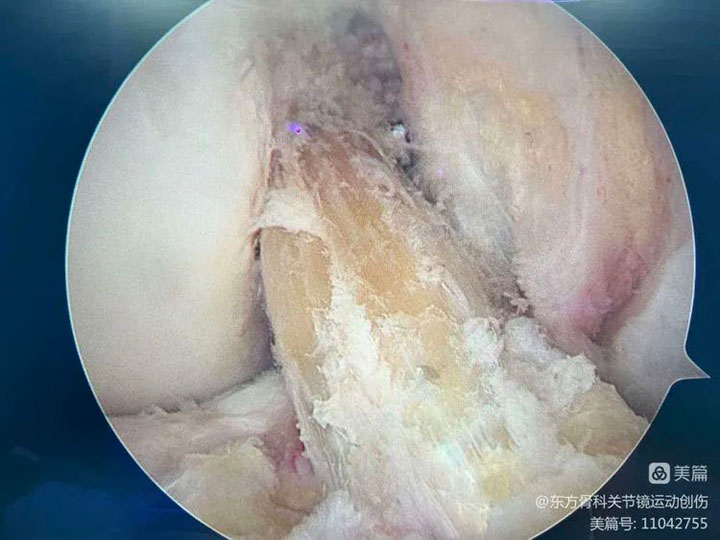

▲手术中探查,前交叉韧带完全撕裂